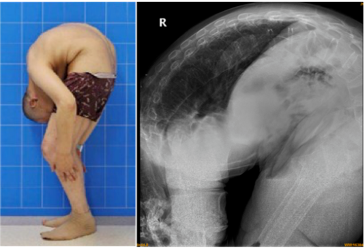

炎晚期,重度脊柱后凸畸形合并双髋关节强直,是临床上罕见的"折叠人"

湖南折叠人:45岁男子脸贴大腿,身体折叠180度,16年后迎来新生

回顾"折叠人"李华:嘴巴离大腿只有两厘米,被敲断4处骨头后获重生